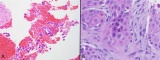

明察秋毫-活检貌似正常的某些肝脏疾病(六)

戈谢病戈谢病(Gaucher disease)是一种常染色体隐性遗传的溶酶体贮积症,可累及肝脏、脾脏、骨髓及中枢神经系统等多个器官。临床表现包括肝脾肿大、骨髓浸润、凝血功能障...